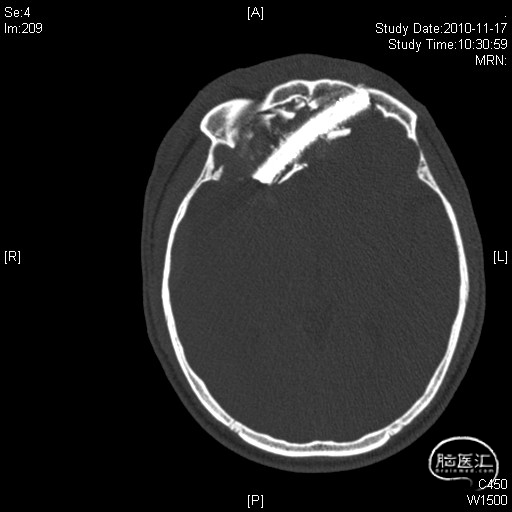

男,42岁,钢筋插入右侧眶部3小时入急诊。

图2. 巨大钢筋自下颌,上颌及前颅底贯穿入颅侧位X片

4. 术前影像学评估非常重要:薄层CT及重建、头颅CTA、头颅MRI,明确异物与颅骨,颅内大动脉及静脉的关系。